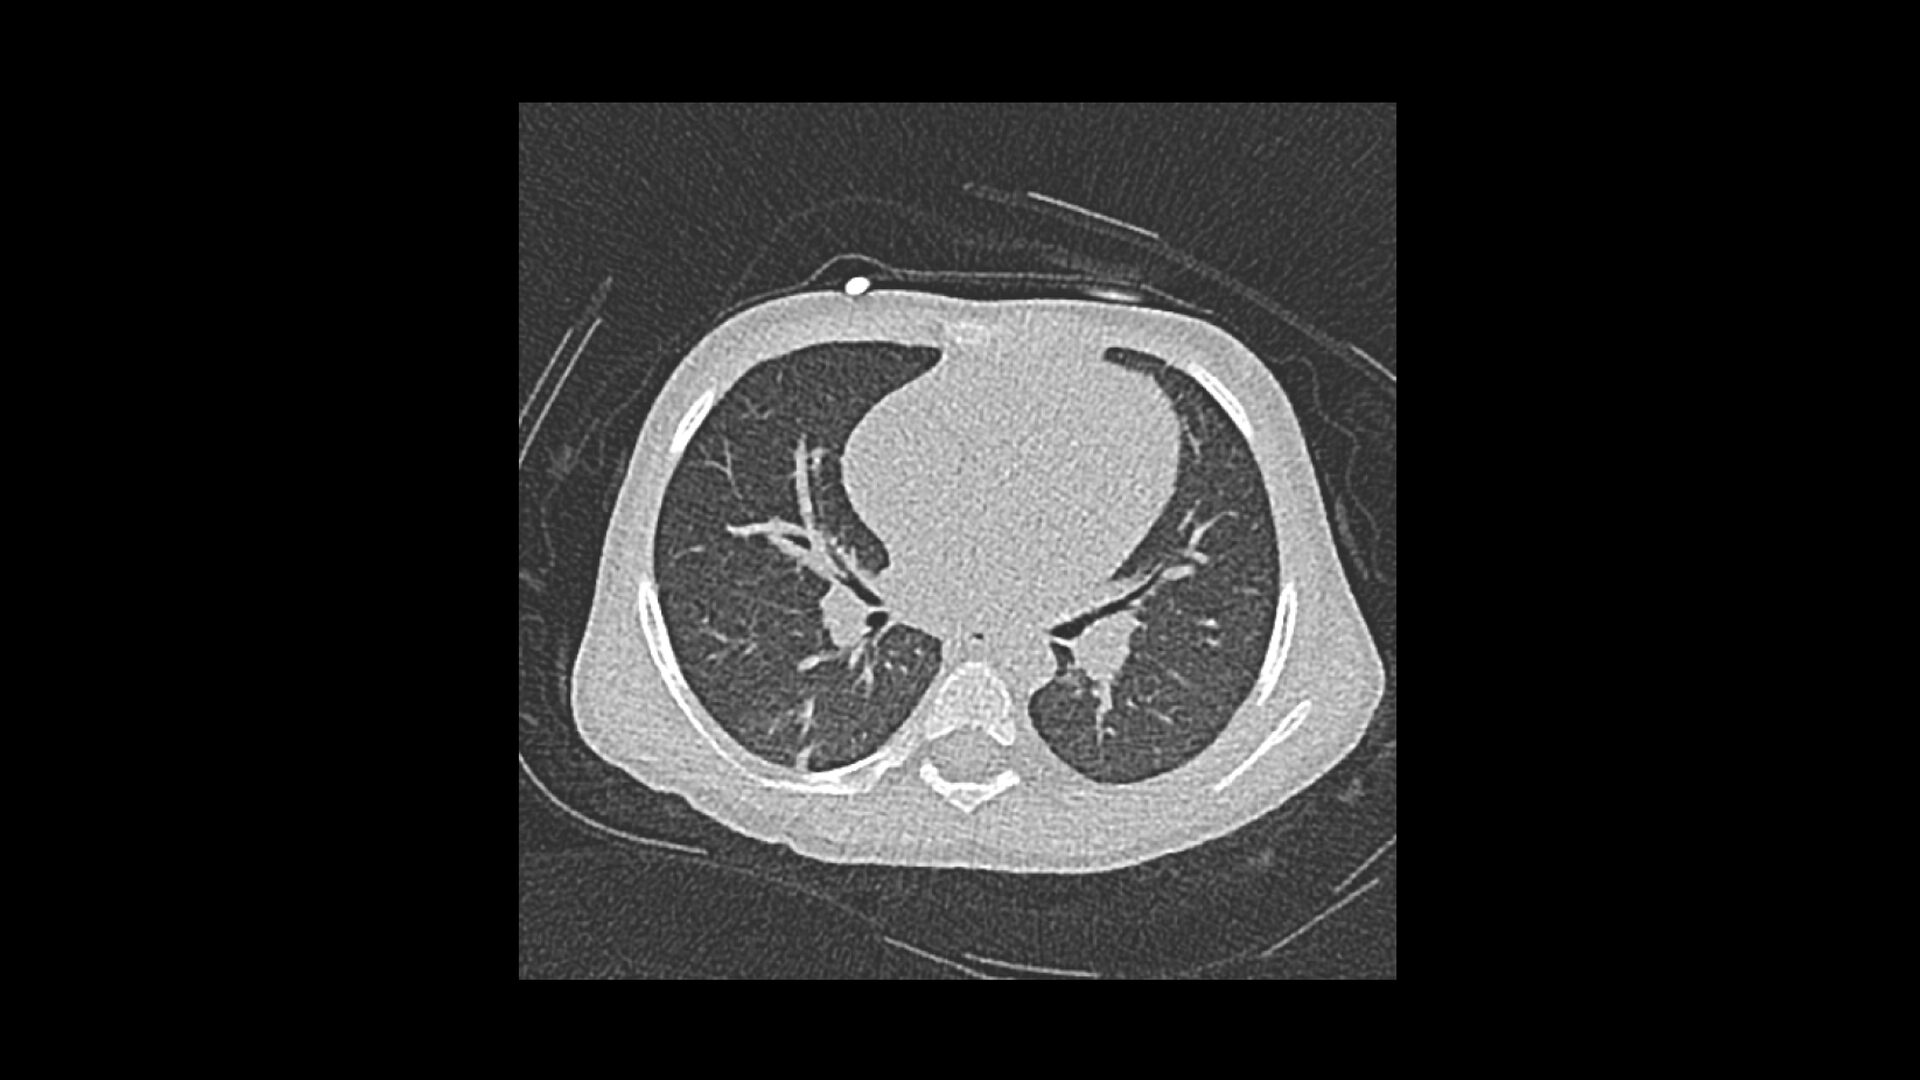

Шаг 2. Раннее выявление заболеваний при низкой лучевой нагрузке

SOMATOM Force позволяет снизить дозу облучения на величину до 50% по сравнению с современным уровнем, характерным для ведущих КТ систем. В сочетании с превосходным пространственным разрешением изображений, исключительной контрастностью мягких тканей и высокой скоростью, это помогает улучшить выявляемость клинически не идентифицируемых патологических изменений, в том числе в легких и толстой кишке.

Фильтры из олова

За счет внедрения фильтров из олова появилась возможность использования низких значений напряжения в трубке Vectron в сочетании с усиленной фильтрацией рентгеновского излучения с помощью технологии Selective Photon Shield, это позволяет улучшить отношение сигнал/шум (SNR) на границе воздуха и мягких тканей. Возможность снижения дозы на величину до 50% при проведении КТ легких и толстой кишки устанавливает новый стандарт исследований асимптоматичных пациентов из группы высокого риска. Превосходный резерв мощности томографа SOMATOM Force позволяет поддерживать высокие значения SNR при низких значениях напряжения трубки для взрослых пациентов и пациентов с избыточной массой тела. Это означает, что рентгенолог может сохранить уровень концентрации контраста, снизив при этом дозу, или, наоборот, снизить концентрацию контрастного вещества при той же лучевой нагрузке. Компания Siemens первой предложила сканирование с низкой дозой сначала при 80 кВ, а затем и при 70 кВ, и сегодня она продолжает расширять границы возможного в компьютерной томографии.